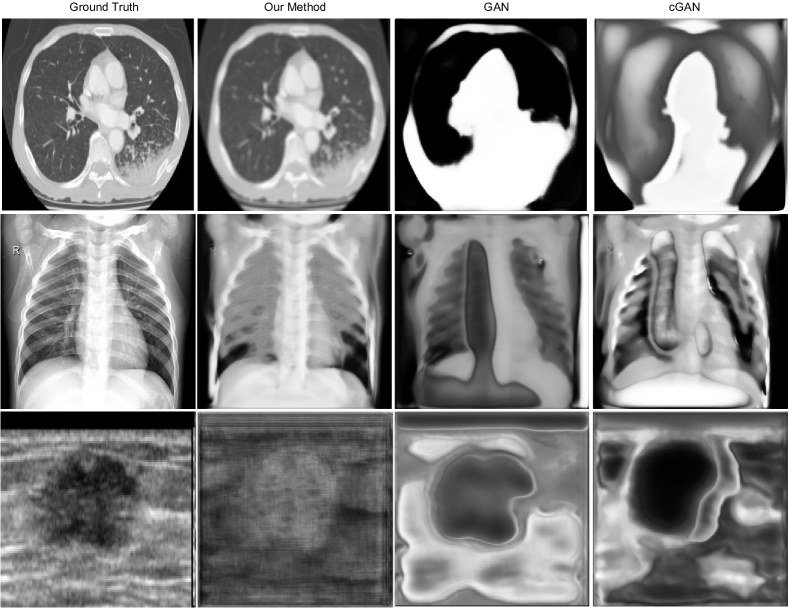

Refer to caption

Figure 2: Generated images on three different domains: Lung CT, Chest X-Ray and Ultrasound. From left to right are: original images, our method, GAN generated image, and conditional GAN generated image. It is obvious that the images generated by our method is more similar with the original ones.

We first compared the performance of image generation among GAN, cGAN, and our method. The results summarized in Table 2 show that our method achieves the best result compared with GAN and conditional GAN on both metrics. In order to better analyze the generated images, we provide the visualization for those generated images. We use three different datasets: Luna, ChestXray8 and BreatUltra as the demo datasets. The visualization can be found on Fig 2. It’s obviously that the image generated by our model are more similar with the ground truth.